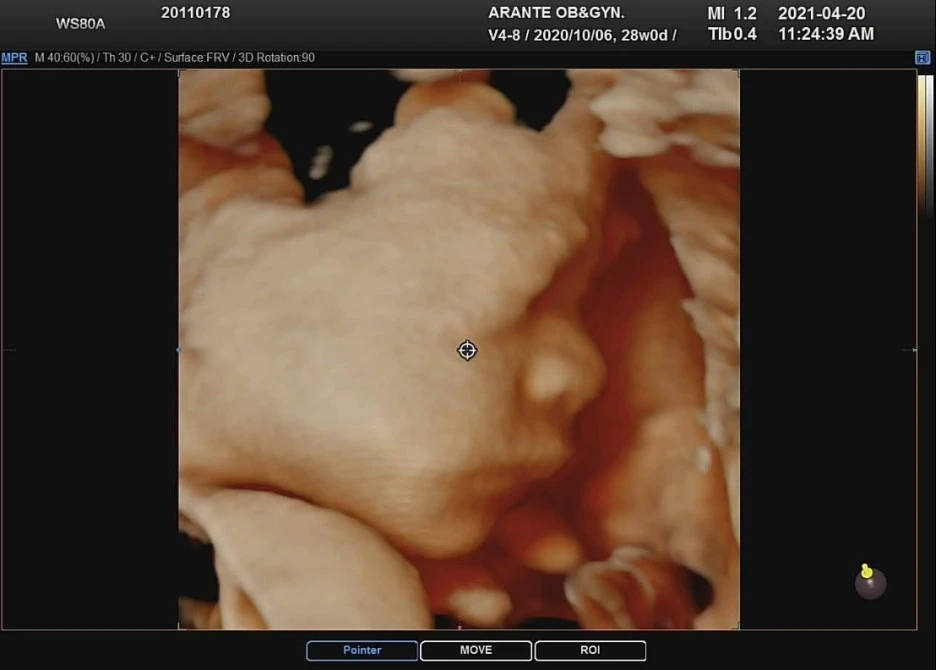

28주 (임신 8개월)에 접어들면 3D 입체 초음파를 할 수 있다는 제안이 들어온다. 이 정도 주수가 차면 아기 얼굴에 살이 통통하게 붙어 실제 얼굴과 비슷한 모습을 볼 수 있게 되기에 아이의 태어나기 전 모습이 궁금한 사람들을 위해 병원이 서비스를 제공하는 것이다. 일반적으로 보는 초음파는 특정 주파수를 이용해서 투과/반사 효과로 측정된 센서 값을 화면상에 보여주기 때문에 센서로부터 멀어지는 단면들을 확인할 수 있고 외형적 기형과 신체 발달과정을 살펴보기엔 적당한 방식이다. 하지만 입체 초음파는 한 번에 다양한 음파를 쏴서 입체적으로 스캐닝을 하는 것이기 때문에 아이한테 안 좋을 것 같지만 짧게 한 번 정도 하는 것은 괜찮다는 병원의 말에 힘을 얻어 우리도 진행하기로 하였다. (호기심의 노예가 만들어낸 자본주의의 필요악 정도로 마음속엔 새겨두기로 하였다.)

첫 시도에서는 라임이가 척추 쪽으로 바라보고 엎드린 자세로 쉬고 있어서 얼굴을 확인하는 것은 실패하였다. 라임이의 자세를 변경하고 활동적으로 만들기 위해서 아내는 의사선생님의 지시에 따라서 밖에 나가서 걷고 계단도 오르락내리락 하고 두 번째 시도를 하였다.

두 번째 시도에서는 엎드린 자세에서 손만 내린 자세. 대 실패였다.

세 번째 시도는 콜록콜록 기침하기, 옆으로 돌아눕기. 허리 들어 올리기 등을 시도하였고 드디어 라임이가 살짝 고개를 돌려주어 옆모습과 앞모습을 살짝 볼 수 있었다.

총 30분 정도가 소요되어서 생각보다 긴 시간 고생한 라임이와 아내를 위해 의사 선생님이 통 크게 컬러 3장에 10컷을 뽑아 주셨다고 한다. (원래는 컬러 2장 정도만 주신다... 은혜로운 아란태 산부인과... 야쓰!)

KakaoTalk_Photo_2021-04-25-22-18-28.jpeg?type=w1 아내의 자는 모습과 동일한 입/코의 모양

정말 너무 사랑스러운 라임이었다. 내가 세상에서 제일 사랑하는 사람과 똑같이 생겼다. 걍 똑같이 생겨서 보자마자 와!!! 하고 말을 할 수밖에 없었다. 생각해 보니 만세를 부르거나 엎드려있는 자세도 아내가 잠을 잘 때의 그것과 닮은 것이 아닐까... 하는 생각이 든다. 양가 어른들에게 사진을 공유드리자 역시 누가 어디를 닮았다는 의견이 분분하게 나왔지만 결론은 라임이가 이미 완성형 미모라고 말해줘서 너무 뿌듯하긴 했다 ㅎㅎ 역시... 예쁜 게 짱이다... 근데 우리 엄마가 진지하게 나를 닮았다는 이야기를 해서 사진을 찾아보니...